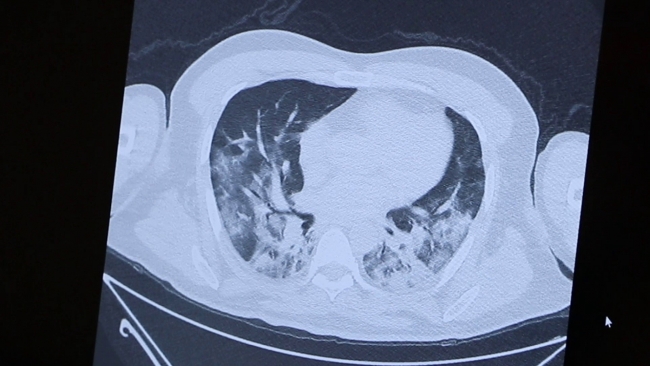

Vatandaşların aşı olması için teşvik edilmesi gerektiğini belirten Prof. Dr. Şevket Özkaya, hastalığın neden olduğu ciddi hasarı bir doktor arkadaşının göğüs filmini göstererek anlattı:

"Doğrusunu söylemek gerekirse bu incelediğimiz tomografi, ölümden kıl payı kurtulan bir doktor arkadaşımın tomografisi. Gördüğünüz gibi kendisi canla başla Covid-19 hastalarını tedavi ederken hastalığa yakalandı. Günlerce hayati tehlike yaşadı. Önce sağlık çalışanlarını aşılayacağız çünkü sağlıkçılar ne kadar güçlü olursa toplumun da o kadar güçlü olacağını düşünüyoruz. Bu görüntüsünü gördüğünüz film de 40’lı yaşlarda bir hastamızın akciğer filmi. Gördüğünüz gibi yaygın bir akciğer tutulumu var. Biz normalde 65 yaş üstünü sokağa çıkmayı yasaklıyoruz ama gördüğünüz gibi 40’lı yaşlarda da çok ciddi akciğer tutulumuyla gelen hastalar oluyor. Bu da bugün kontrole gelen akciğeri pırıl pırıl olan bir hastamız. Herkes bu kadar şanslı olmuyor. Bildiğiniz gibi 65 yaş üstü vatandaşlarımızı bu salgında çok fazla kaybettik. Onlar şu an hala evde hapisler. Toplumda ne kadar çok kişi aşılanırsa bu esaretten kurtulacağımızı düşünüyoruz.”